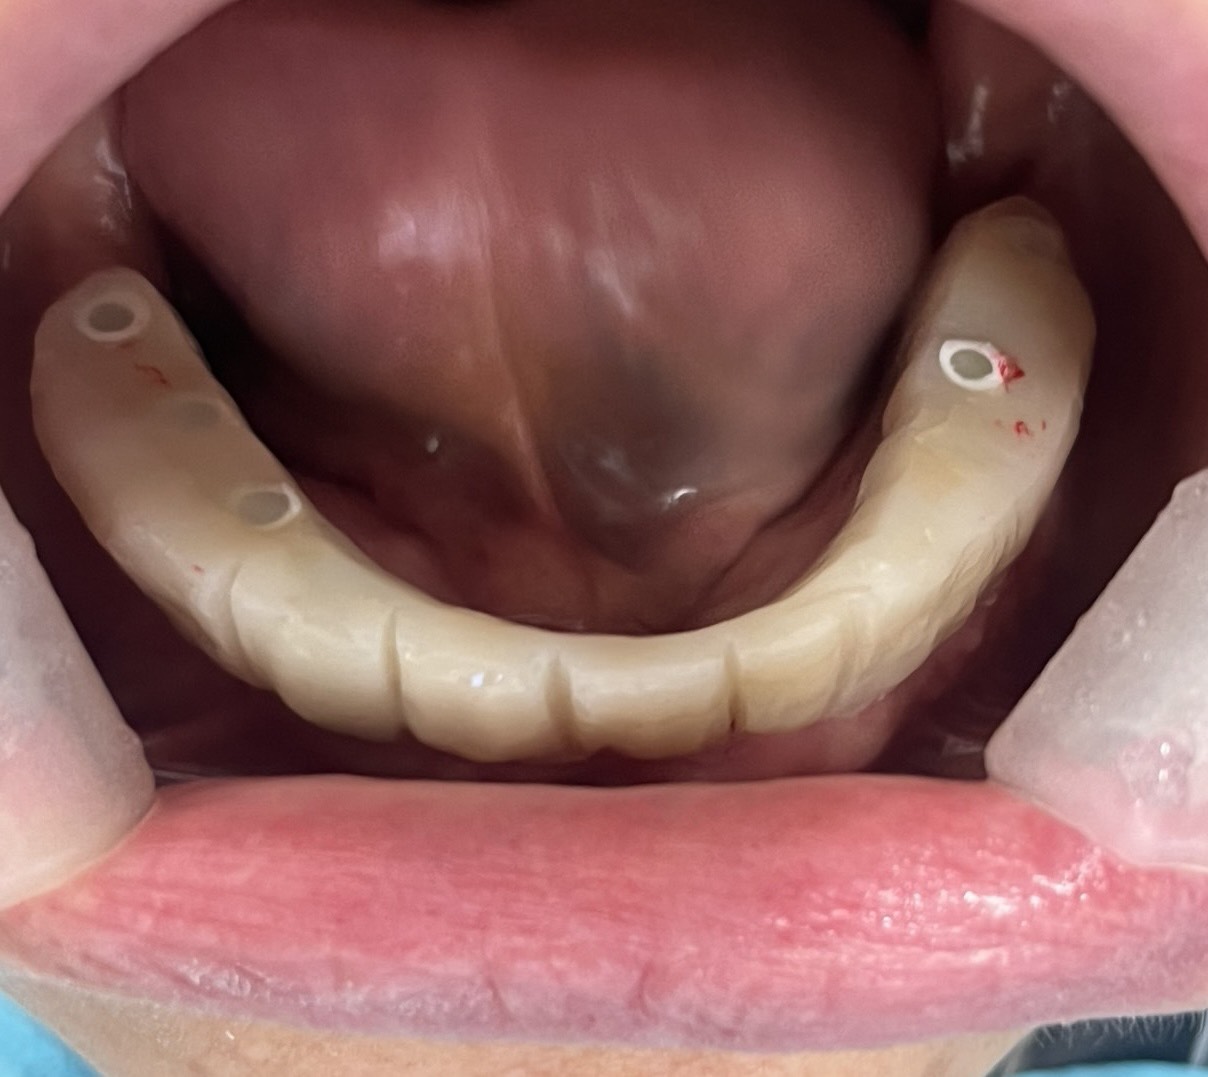

一位患者特地從外州飛到拉斯維加斯,評估後當天決定進行全口植牙。整個療程不到兩小時,即拔即植即固定臨時牙。

手術當天完成全口掃描,四個月後更換為最終固定假牙。這段期間,患者維持良好的生活品質,醫師也能安心照護,不用每天提心吊膽、接不完病患來電。